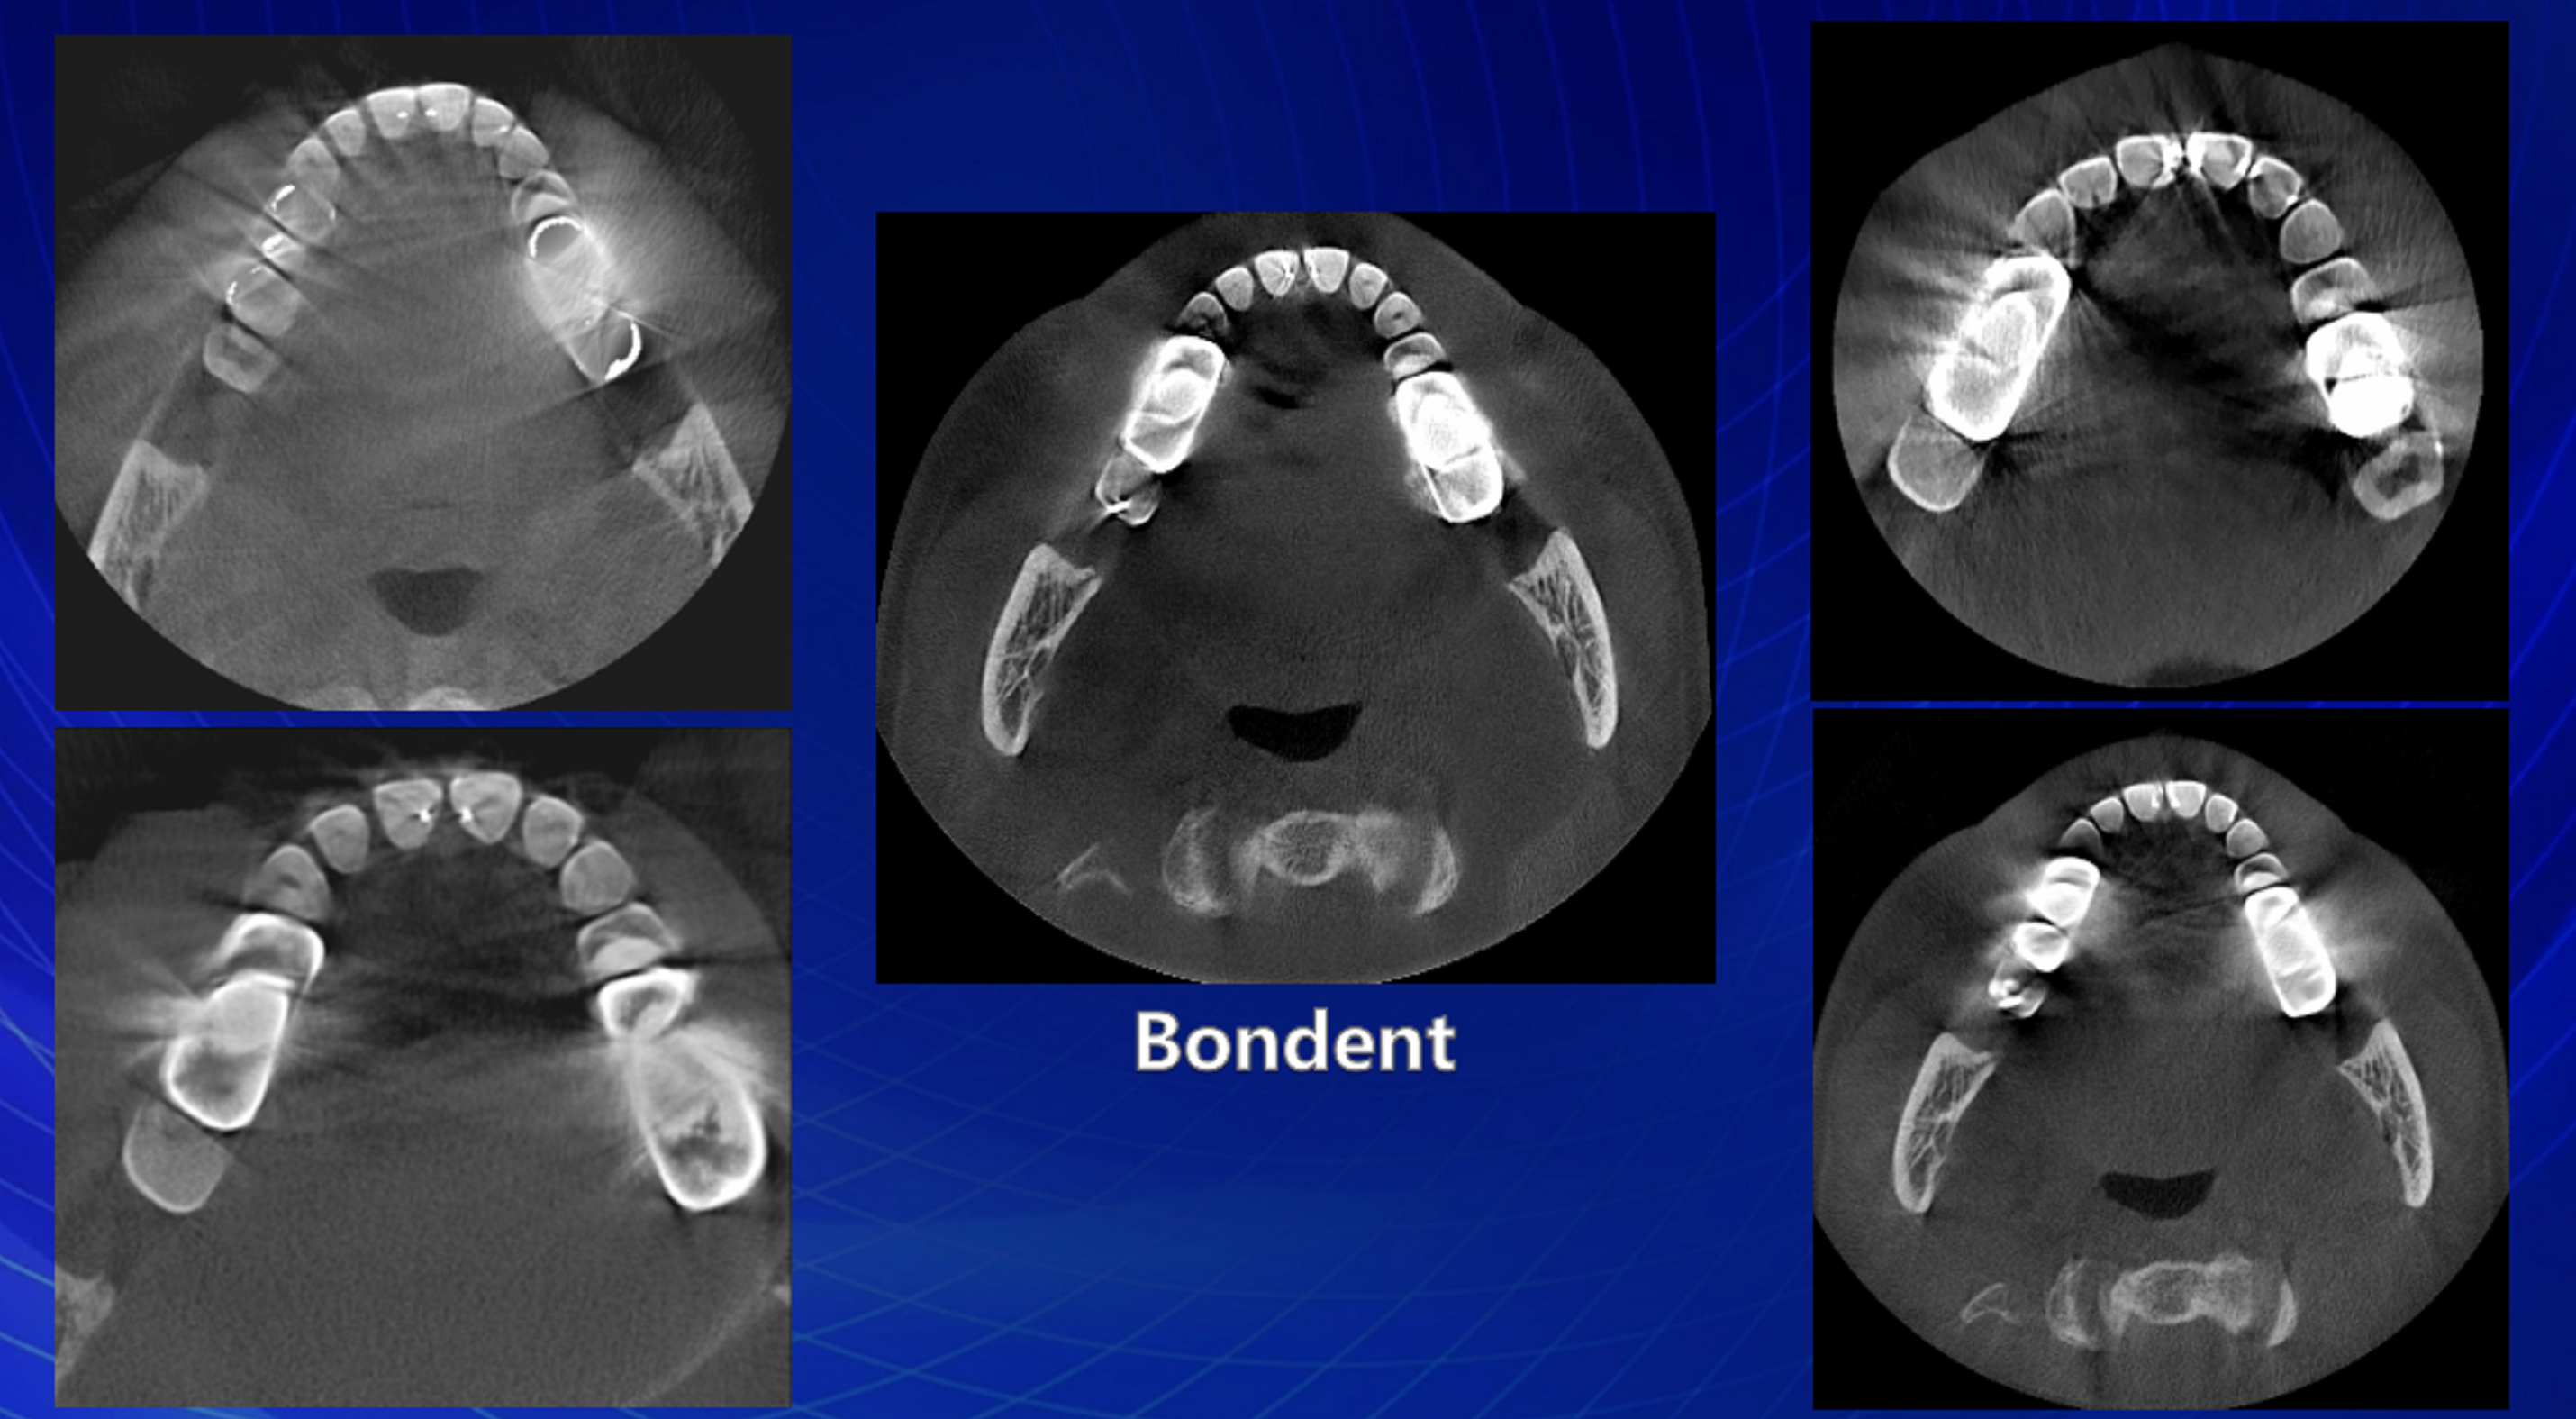

胡xx 20210306 智齿cbct 137xxxx0605

图片尺寸840x459